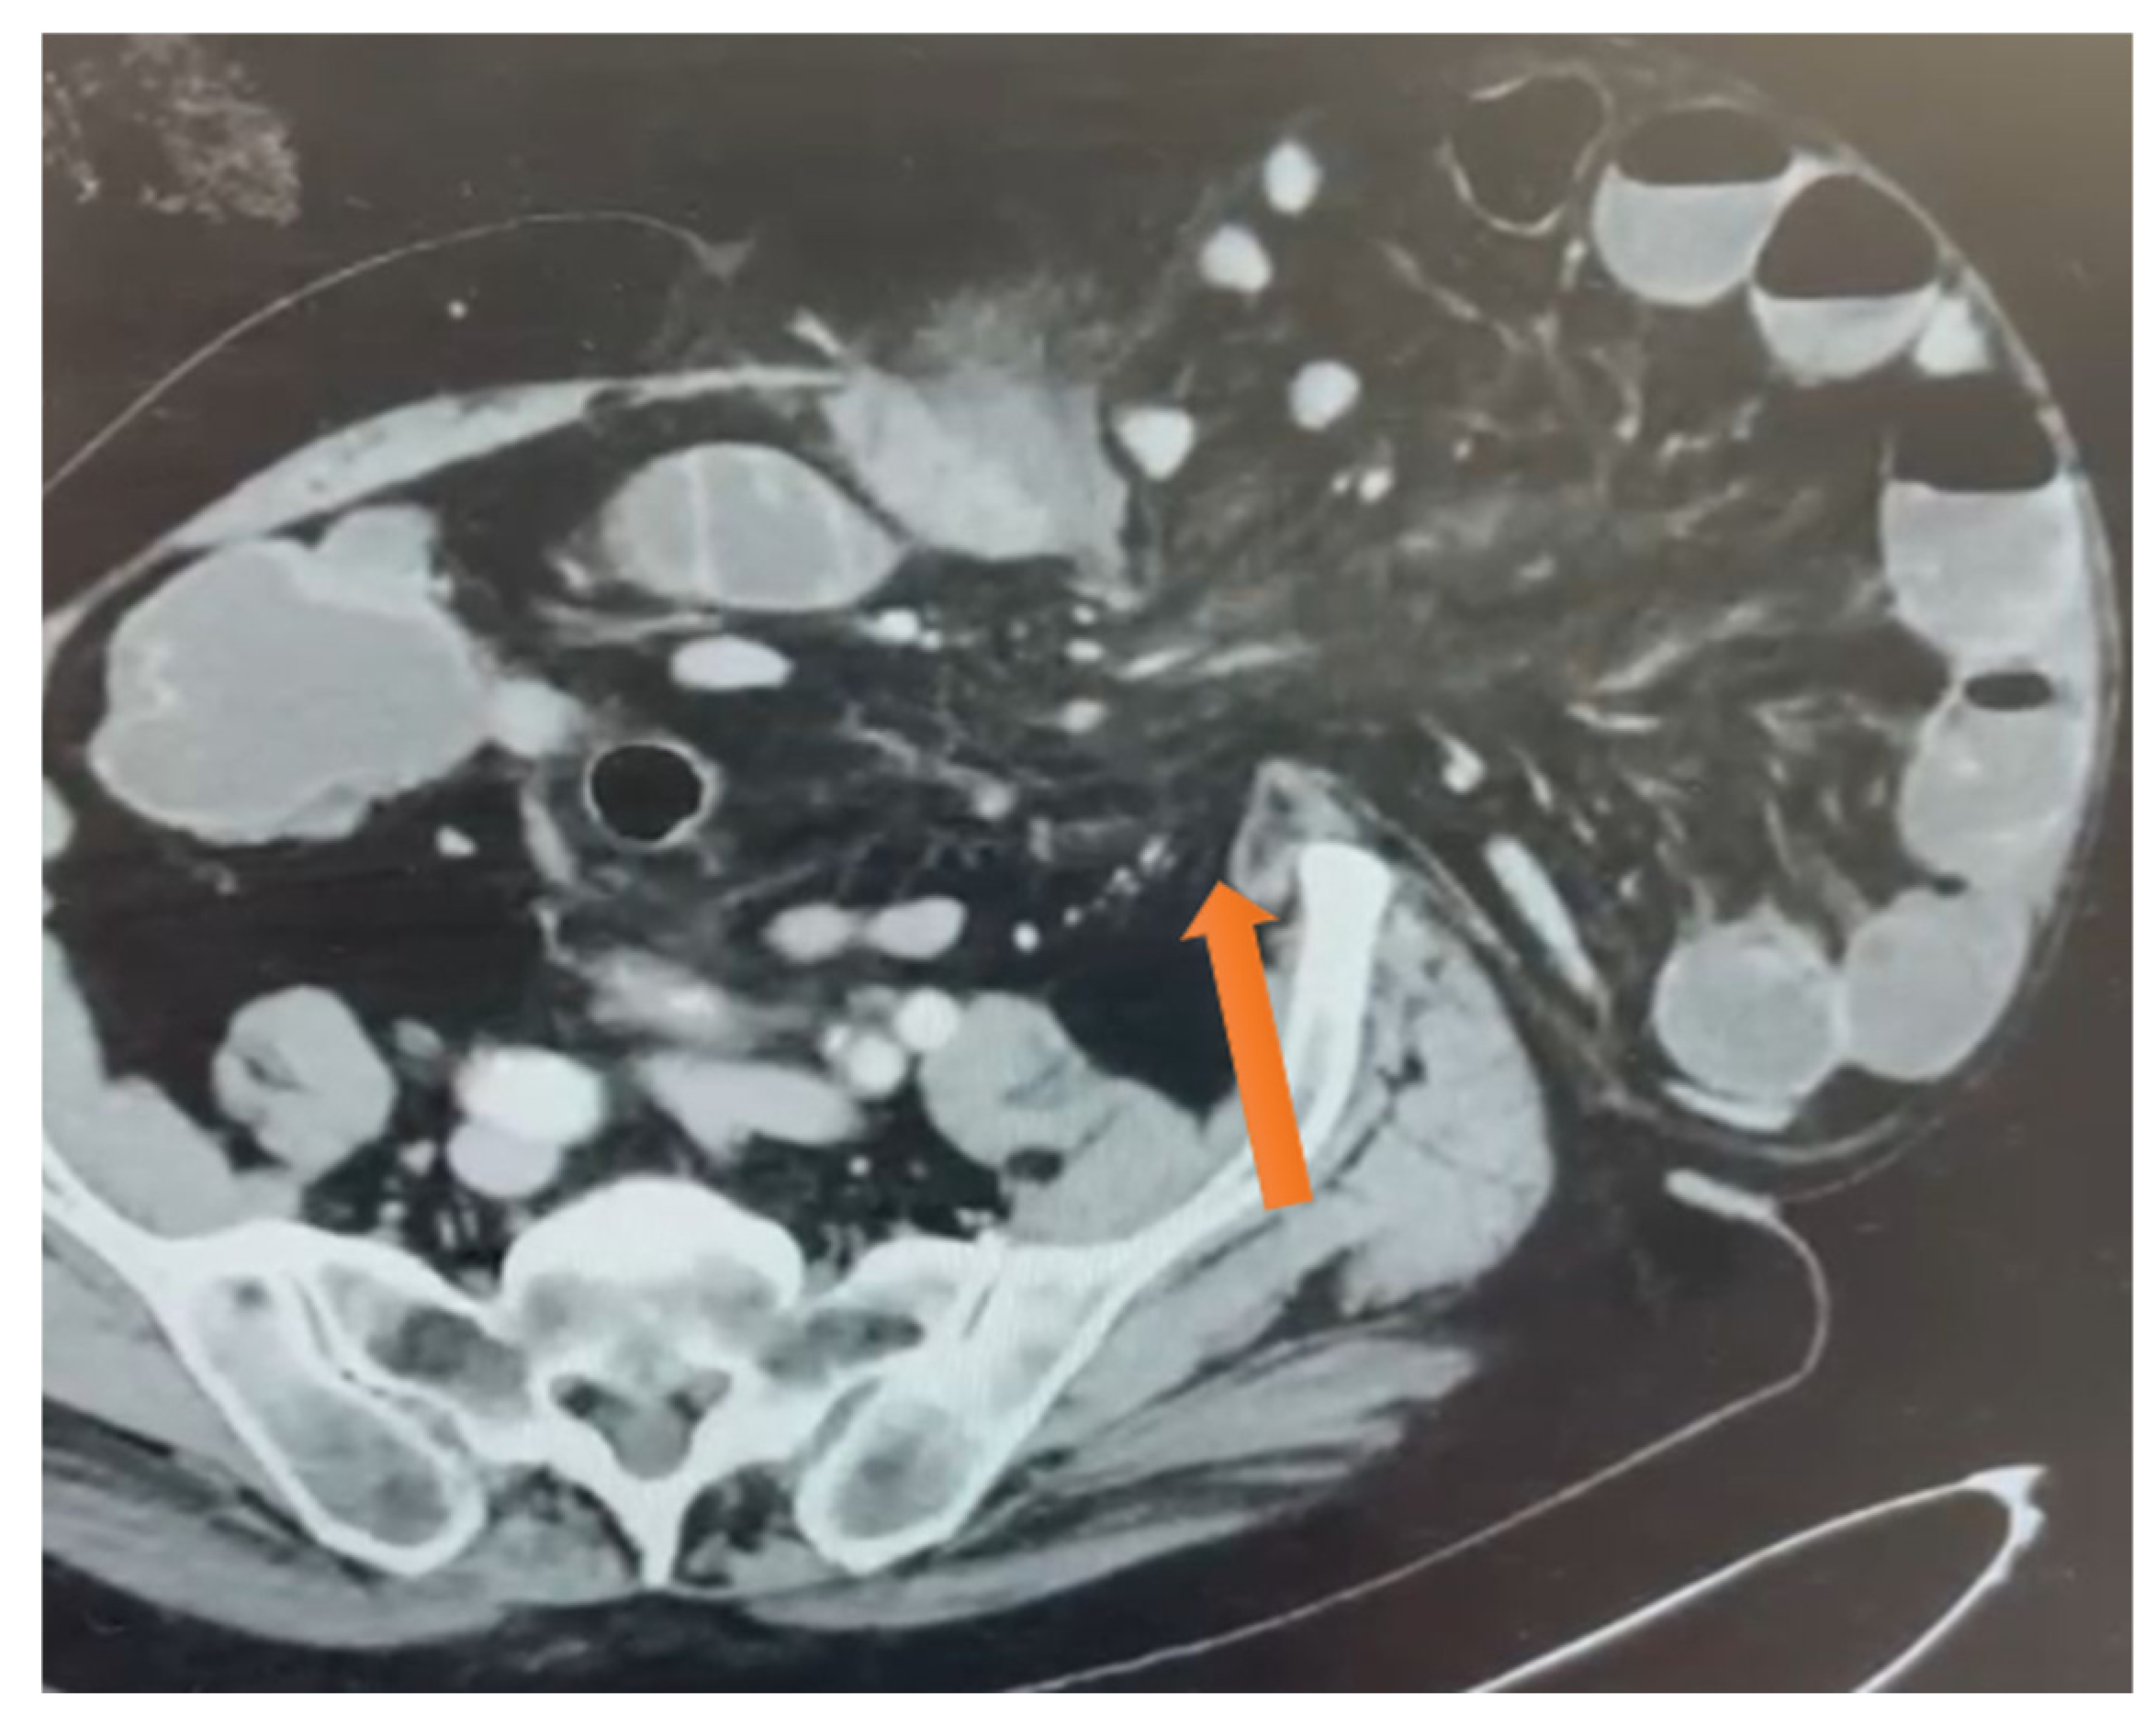

Figure 1.

Axial CT scan showing the neck of the hernia defect in the lateral abdominal wall at the level of the iliac spine see the orange arrow indicates the neck of the hernia.